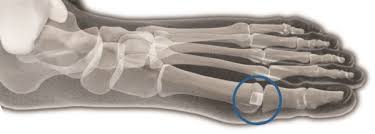

The Cartiva® Synthetic Cartilage Implant (Cartiva SCI) is a man-made implant that is made of a soft plastic-like substance and salt water. These materials are combined and moulded into a solid, slippery, and durable implant.

The Cartiva SCI is intended to treat painful arthritis in the joint of the big toe.

• Hemi-arthroplasty: A surgery that replaces part of your joint with metal or plastic parts to serve as the new surface of the first metatarsophalangeal head.

• Total Joint Replacement: A surgery that replaces your joint with metal and plastic parts to replace both sides of the MTP joint.

• Fusion (arthrodesis): A surgery where the two sides of the MTP joint are cleared of cartilage. The two bones are held together with plates and/or screws so that the bones grow together.